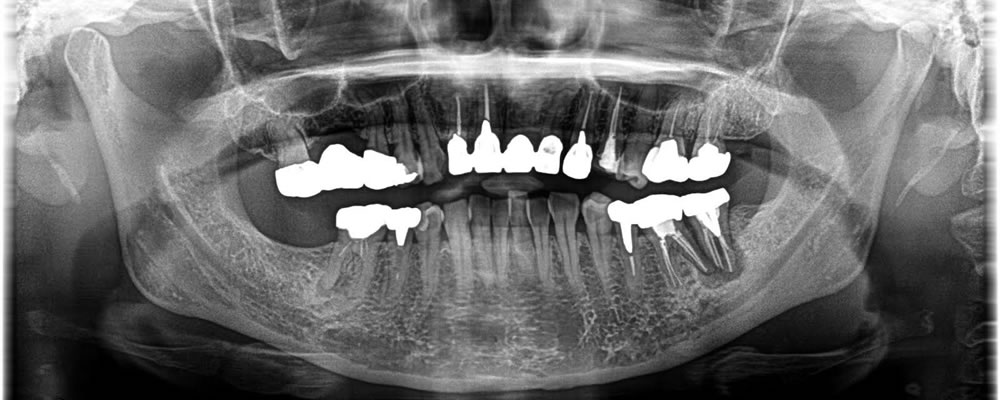

ブリッジ部分をインプラントで治療した症例

50代

男性

痛みのある歯を抜歯後にインプラントで治療した症例

20代

女性

膿が溜まった歯を抜歯後にインプラントで治療した症例

30代

欠損部分に実施したインプラント治療の症例

40代

痛みのある奥歯をインプラントで治療した症例